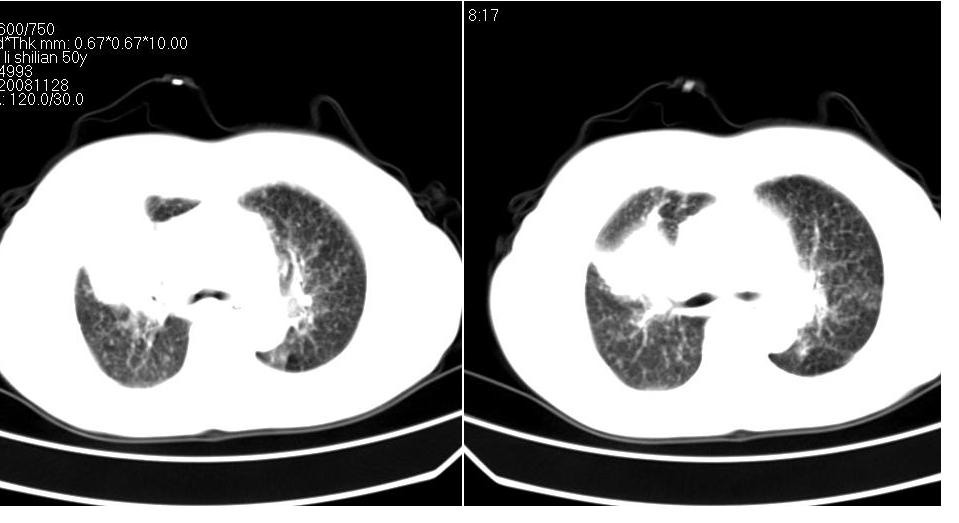

标题: CT16839:胸部CT平扫

女 50岁,在其他医院确诊肺癌.

支持 右肺上叶肺癌并两肺及纵隔转移。